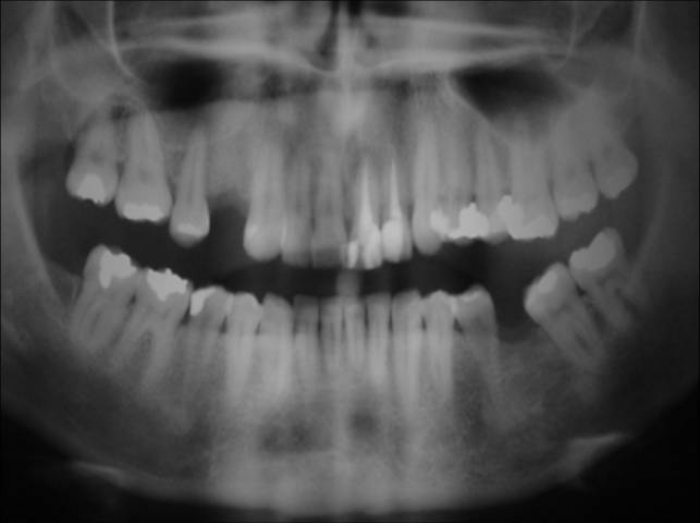

Rx e imagem da prótese fixa em porcelana sobre implante